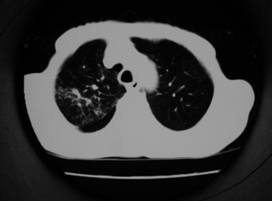

以下是引用同在2007-1-27 14:13:00的发言:[br]支持右侧中央型肺癌伴阻塞性病变.

以下是引用zjzjr在2007-1-27 16:56:00的发言:[br]支持右肺中心型肺癌伴阻塞性肺炎.